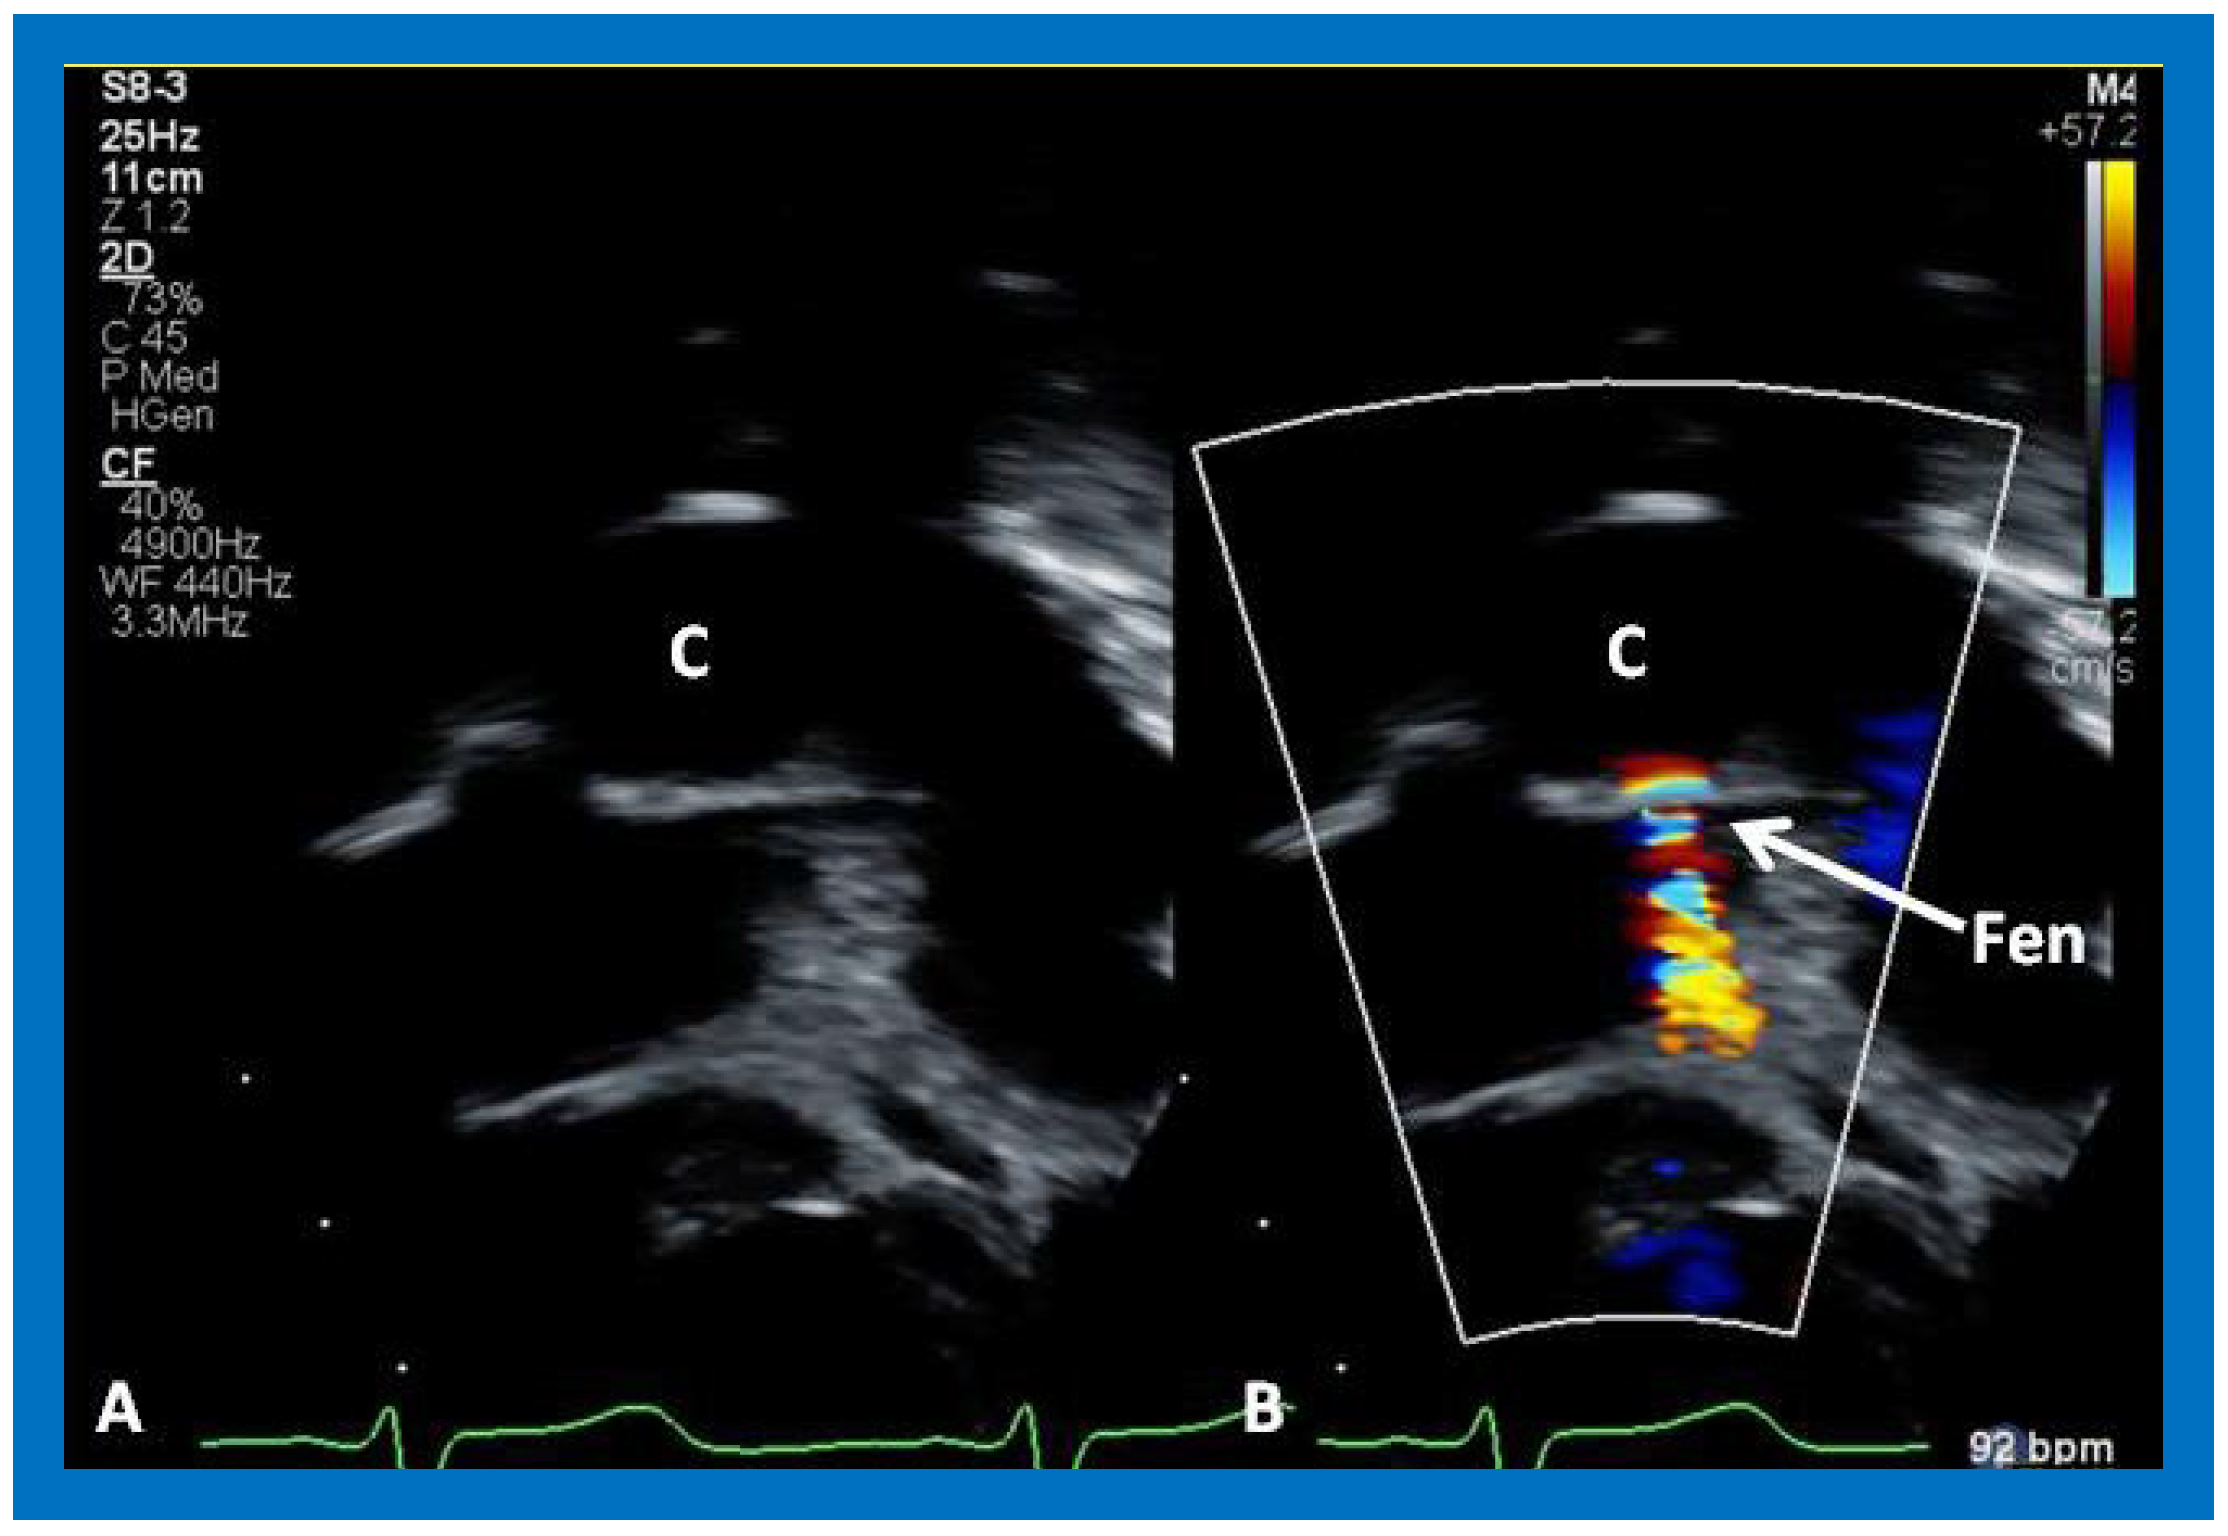

Surgically created fenestrations (Figure 50, Figure 51, Figure 52 and Figure 53) can also be demonstrated by color Doppler studies and the mean gradient across the fenestration (Figure 52 and Figure 53) is helpful in determining the physiologic state; a mean gradient of 4 to 8 mmHg is considered adequate.

Figure 23. Selected echocardiographic video frames demonstrating pulmonary artery band (PAB) with narrow diameter by color flow (A) and a high gradient (88 mmHg) by continuous wave Doppler (B) are shown.

Applsci 11 09472 g023